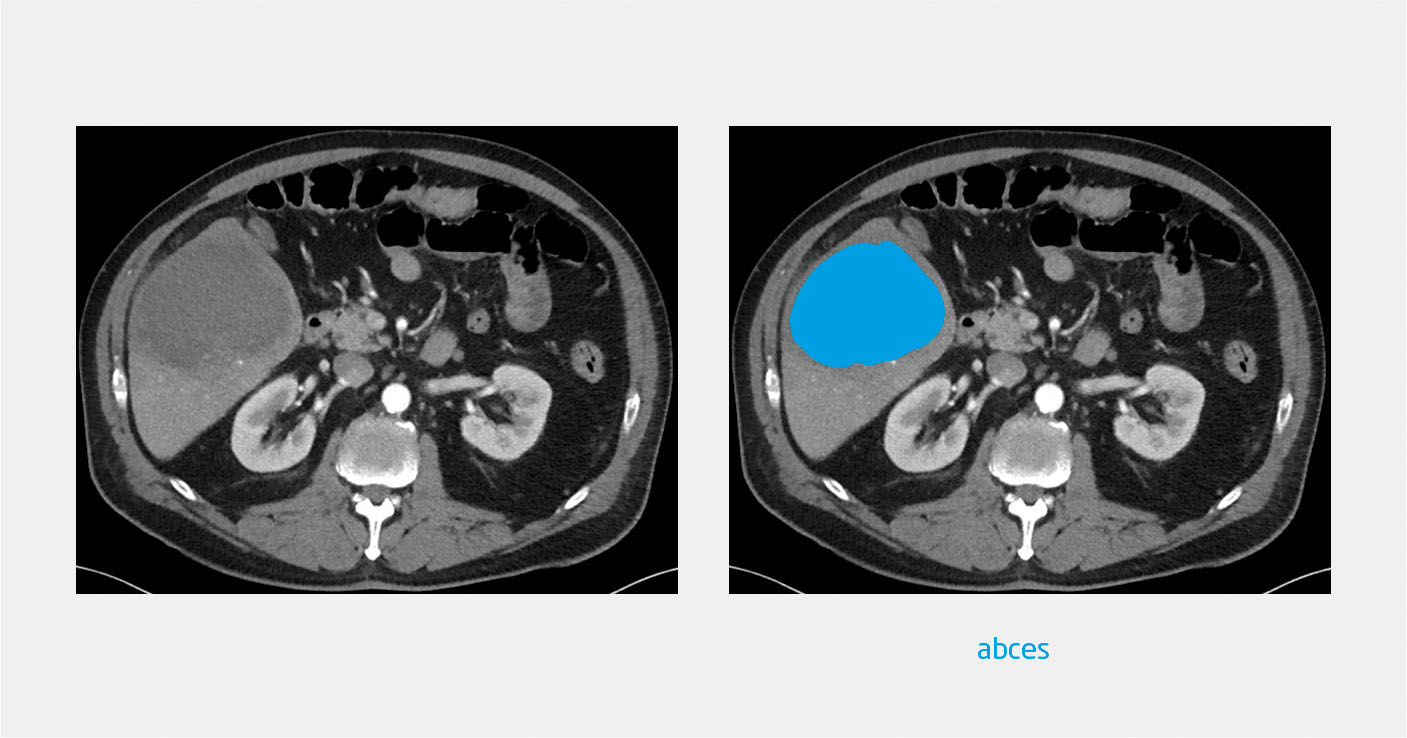

CT van het abdomen toonde een grote afwijking in de lever, verdacht voor abces (figuur 2). Op empirische gronden kreeg de patiënt amoxicilline/clavulaanzuur (1200 mg 4 dd iv) voorgeschreven, gecombineerd met ciprofloxacine (400 mg 2 dd iv). Bij drainage van het abces werd bruin, stroperig vocht geaspireerd. Vanwege dit aspect – ‘ansjovispasta’ genoemd – in combinatie met de reisanamnese overwogen wij de diagnose ‘ E. histolytica -infectie. Aanvullend microscopisch onderzoek en PCR van het abcesvocht en PCR op de feces bevestigden deze diagnose. De behandeling werd voortgezet in de vorm van metronidazol (750 mg 3 dd gedurende 7 dagen), gevolgd door clioquinol 250 mg 3 dd gedurende 10 dagen, waarna de patiënt klachtenvrij werd.

Figuur 2

Een groot abces in de lever bij patiënt C

Figuur 2 | Een groot abces in de lever bij patiënt C

CT-scan van het abdomen (transversale coupe). Uit microscopisch onderzoek en PCR van het abcesvocht bleek het om een amoebenabces te gaan, veroorzaakt door Entamoeba histolytica.